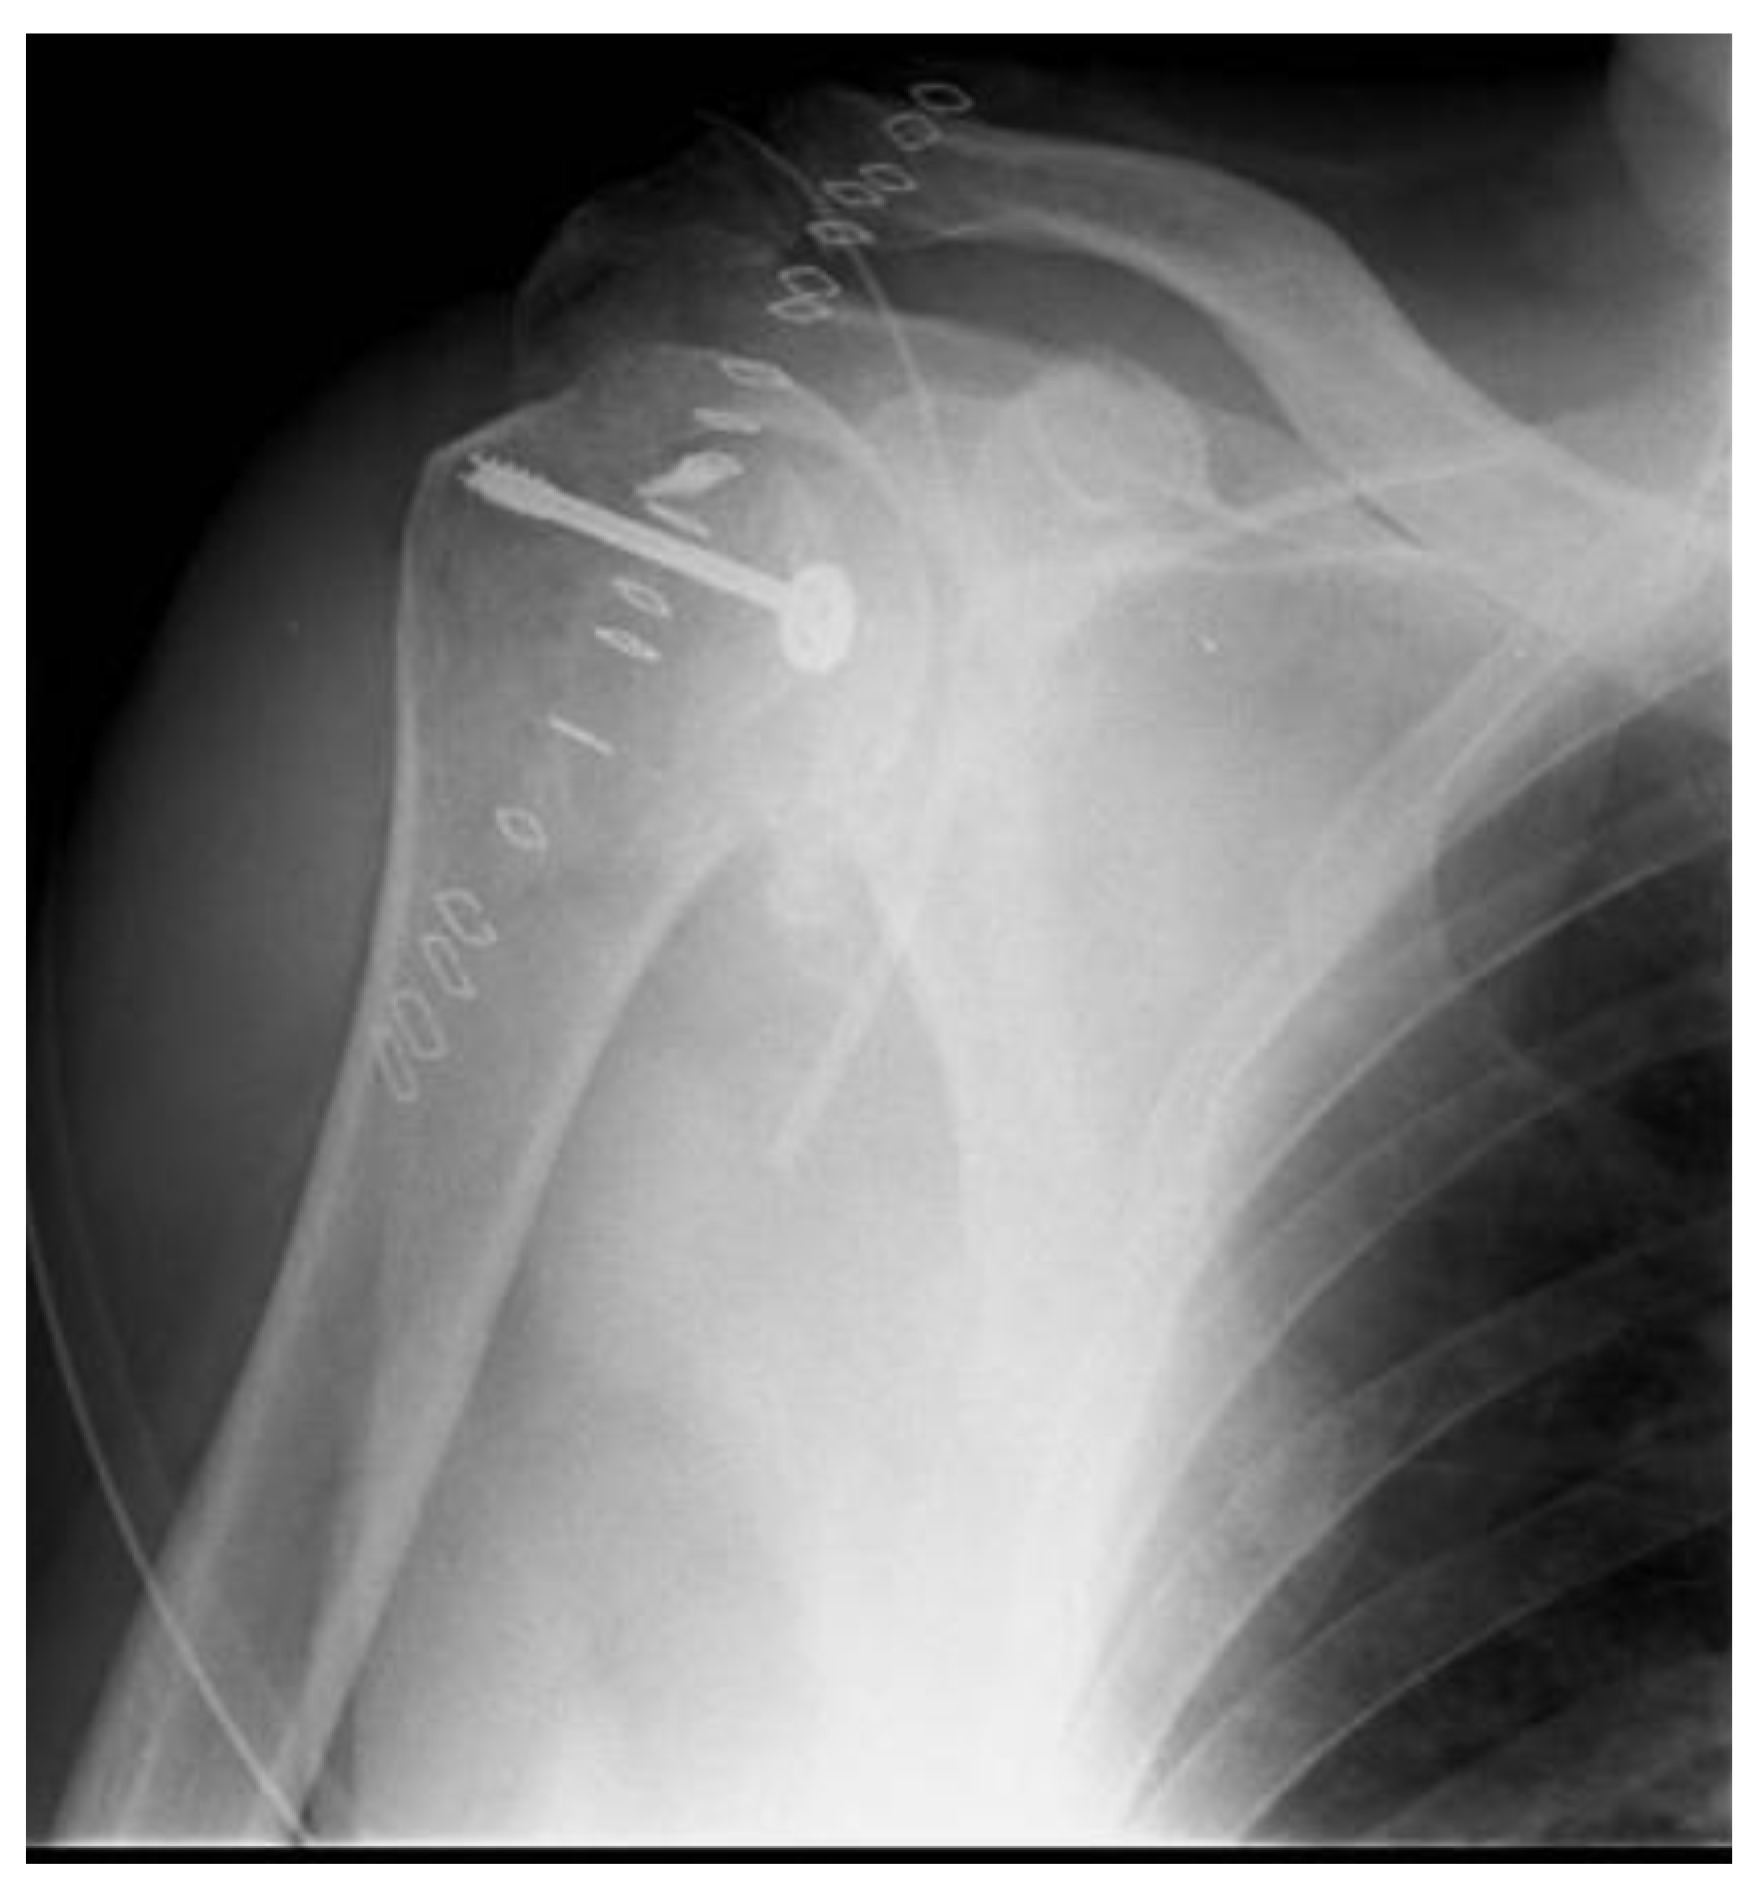

Posterior Shoulder Dislocation with Engaging Reverse Hill–Sachs Lesion: A Retrospective Study of Ten Patients Treated with Arthroscopy or Open Reduction and Stabilization

Ippolito, G.; Zitiello, M.; De Marinis, G.; D’Angelo, F.; Surace, M.F.; Ronga, M.; Sepe, V.; Garro, L.; Faoro, L.; Ferraro, S. Posterior Shoulder Dislocation with Engaging Reverse Hill–Sachs Lesion: A Retrospective Study of Ten Patients Treated with Arthroscopy or Open Reduction and Stabilization. J. Clin. Med. 2021, 10, 1410. https://doi.org/10.3390/jcm10071410